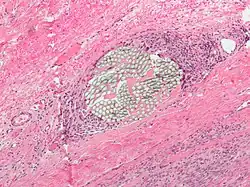

Micrograph of a H&E stained tissue section showing a non-absorbable multi-filament surgical suture with a surrounding foreign-body giant cell reaction

Suture material is often broken down into absorbable thread versus non-absorbable thread, which is further delineated into synthetic fibers versus natural fibers. Another important distinction among suture material is whether it is monofilament or polyfilament (braided) [2]